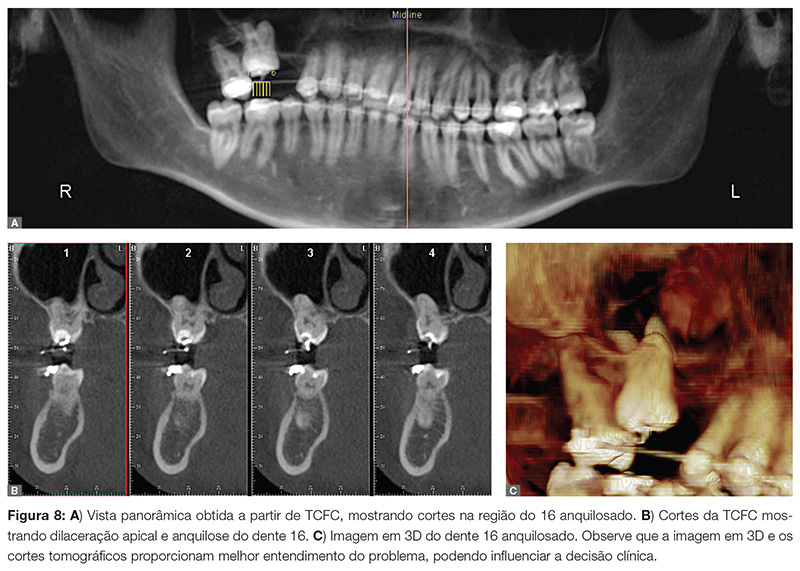

Mossaz et al.8 realizaram TCFC em 82 pacientes com dentes supranumerários para avaliar a localização e as características morfológicas desses dentes e para verificar a extensão de reabsorção radicular dos dentes adjacentes. Após a análise das imagens por dois ortodontistas, independentemente, dados sobre os dentes retidos e adjacentes foram compilados e estudados. Eles concluíram que o uso de TCFC proporciona uma informação 3D precisa sobre a localização e a forma do dente supranumerário retido, assim como a prevalência e o grau de reabsorção radicular dos dentes vizinhos, com moderada a alta correlação entre os examinadores (Fig. 7, 8, 9).

» Dentes anquilosados.